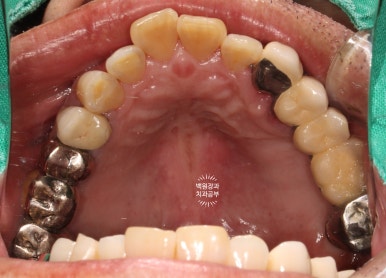

저희 치과에 내원하셨을 당시 입안 사진입니다.

사실 사진만으로는 그 불편함을 느끼기가 어려우실텐데요, 아래는 비교적 최근에 제작된 깔끔한 전체틀니를 사용하고 계셨고, 위 어금니는 만성치주염에 이환되긴 했지만 형태를 모두 갖추고 있었습니다.

위턱 교합면 사진입니다.

오른쪽의 까만색으로 보이는 부위들은 교합조정을 위한 교합종이의 색깔입니다.

충분히 깔끔한 모양새고...

이가 없던 부위는 이가 생겼으니 가장 큰 변화를 이루어냈다고 생각해야겠네요.